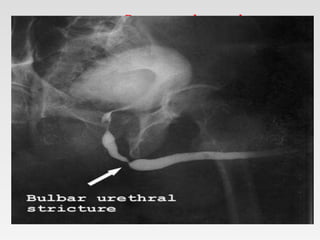

• Retrograde urethrogram

• Antegrade cystourethrogram

Retrograde urethrogram